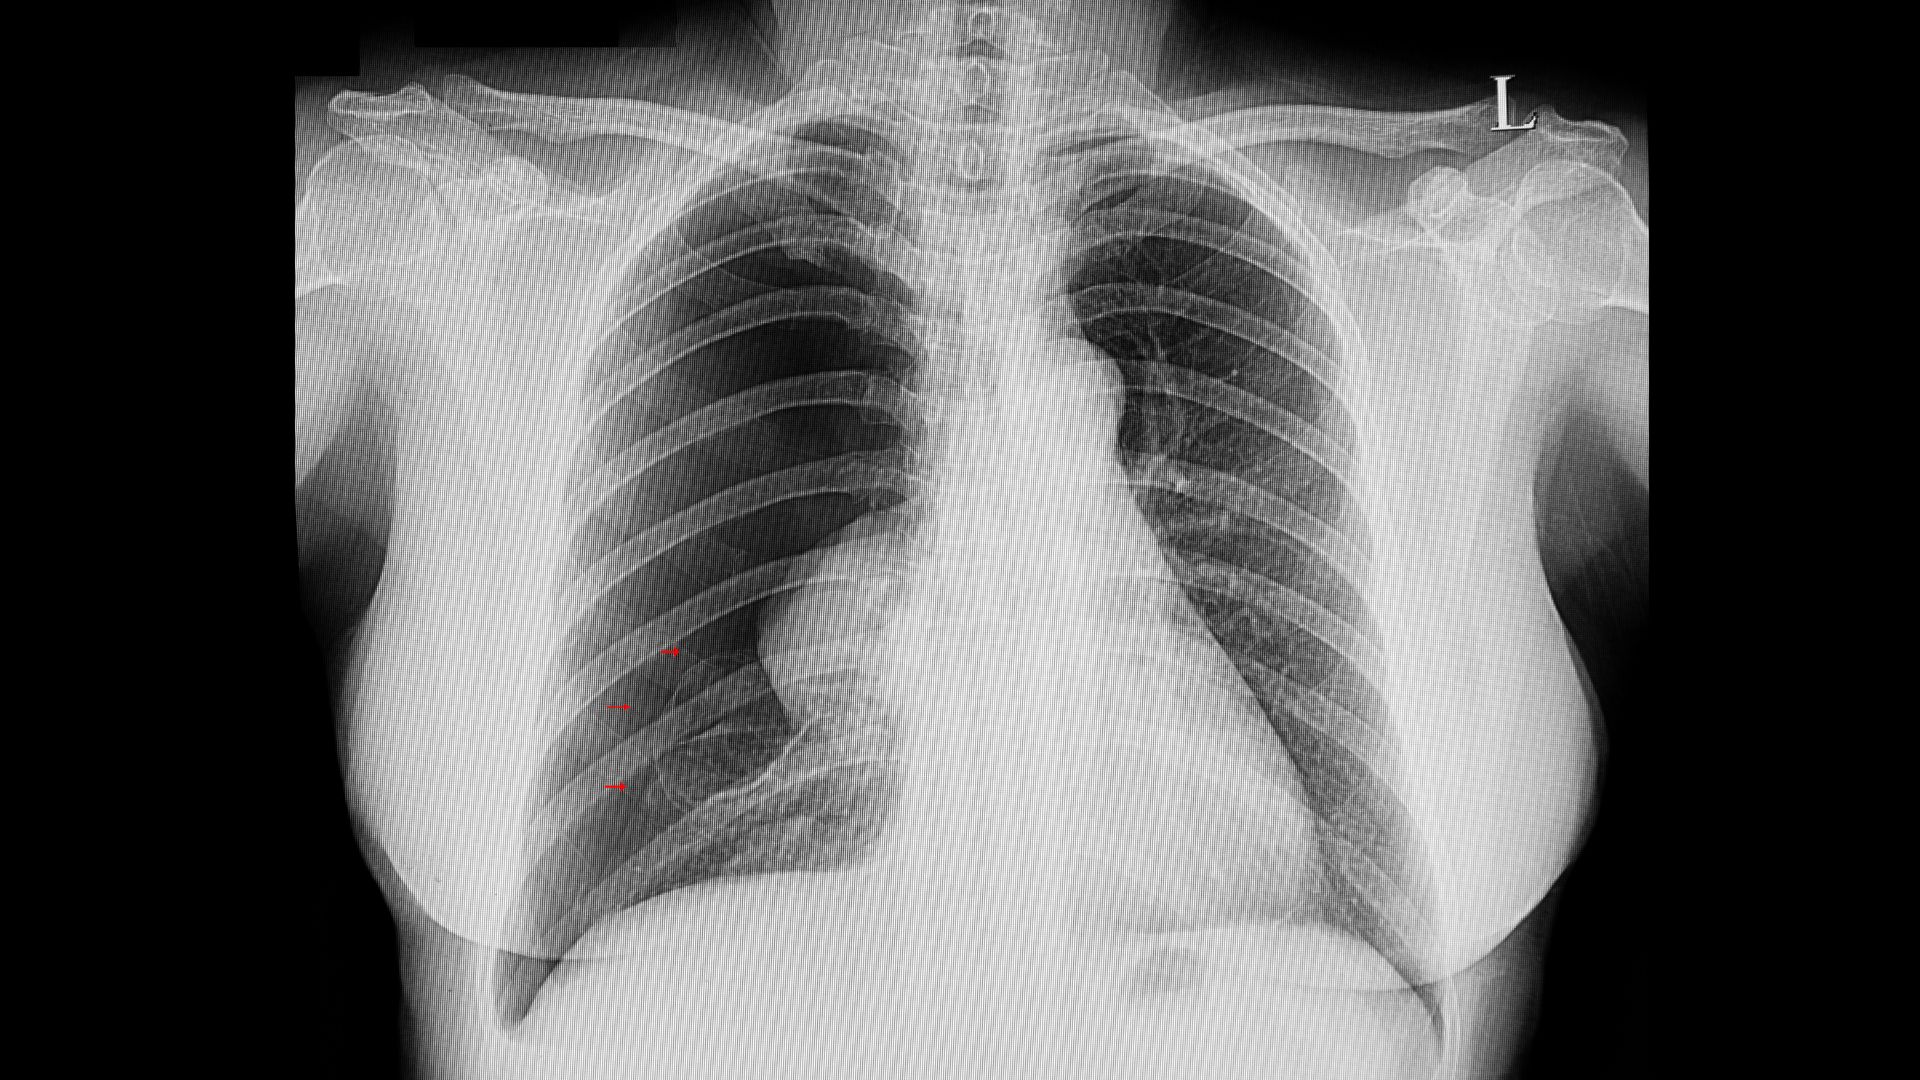

Tràn khí màng phổi

Tràn khí màng phổi là biến chứng thường gặp và có thể đe dọa tính mạng. Khi các phế nang bị căng quá mức do việc hít vào không đầy đủ khí, chúng trở nên mỏng manh và dễ vỡ, từ đó làm rò rỉ khí vào khoang màng phổi. Triệu chứng chính bao gồm đau ngực đột ngột và khó thở dữ dội. Việc  đối phó với tràn khí màng phổi  ngay khi phát hiện dấu hiệu có thể cứu sống bệnh nhân bằng cách cấp cứu kịp thời để ngăn ngừa suy hô hấp nặng và các biến chứng nguy hiểm khác.

Tràn khí màng phổi là biến chứng cấp cứu có thể xảy ra đột ngột